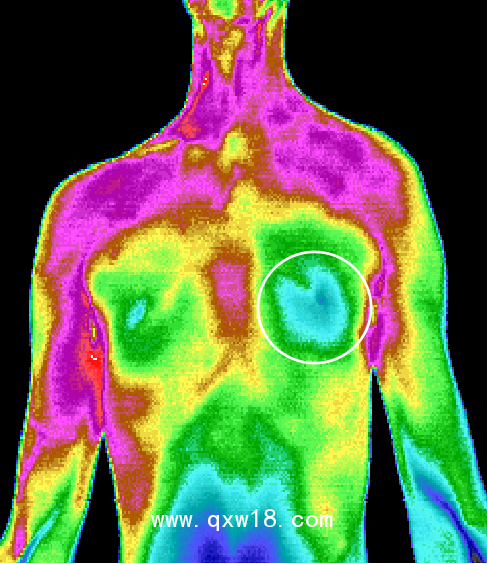

中醫(yī)熱CT是醫(yī)學(xué)技術(shù)和紅外攝像技術(shù)、計(jì)算機(jī)多媒體技術(shù)結(jié)合的產(chǎn)物,人體是一個(gè)天然的生物發(fā)熱體,由于解部結(jié)構(gòu)、組織代謝、血液循環(huán)及神經(jīng)狀態(tài)的不同,機(jī)體各部位溫度不同,形成不同的熱場,中醫(yī)熱CT被動(dòng)接收人體組織細(xì)胞代謝熱源,可以反映出人體局部0.05°C~0.1°C的溫度微弱變化,0介入、0損傷、0輻射、0痛苦,結(jié)合Al智能分析可將傳統(tǒng)中醫(yī)通過“四診八綱”等原始手段獲取的人體信息,通過數(shù)值化和可視化的彩色圖像,形象客觀的呈現(xiàn)出來觀測臟腑的寒熱狀態(tài)、經(jīng)絡(luò)氣血流通情況、中醫(yī)藥效果的可視化觀察,針灸,推拿按摩,刮癡拔罐等治療的指導(dǎo)及效判定、參與九種體質(zhì)的評(píng)測,拓展了中醫(yī)四診,增加了中醫(yī)的“第五種診斷方法”,推動(dòng)中醫(yī)現(xiàn)代化的發(fā)展,被形象的比喻成“扁鵲之眼”

???中醫(yī)熱CT檢測最重要的一個(gè)優(yōu)勢就是早期預(yù)警,X光、B超、CT等檢測技術(shù)都屬于結(jié)構(gòu)影像技術(shù),只有在疾病形成病灶之后才能發(fā)現(xiàn)疾病。而疾病在出現(xiàn)組織結(jié)構(gòu)和形態(tài)變化之前,細(xì)胞代謝就會(huì)發(fā)生異常。中醫(yī)熱CT可以反映出人體后部0.05°C~0.1C的溫度微弱變化,因此能更早地發(fā)現(xiàn)問題。檢測所得為高清晰度彩色圖像,具有更直觀、更形象的特點(diǎn),結(jié)合AI智能分析,所得結(jié)果精準(zhǔn)度更高,成為了目前我們認(rèn)知亞健康最有力的測評(píng)技術(shù)。

紅外熱CT檢測最重要的一個(gè)優(yōu)勢就是早期預(yù)警。X光、B超、CT等檢測技術(shù)它們都屬于結(jié)構(gòu)影像技術(shù),只有在疾病形成病灶之后才能發(fā)現(xiàn)疾病。而疾病在出現(xiàn)組織結(jié)構(gòu)和形態(tài)變化之前,細(xì)胞代謝就會(huì)發(fā)生異常。醫(yī)用紅外熱CT可以反映出人體局部0.05°C ~ 0.1°C的溫度微弱變化,因此能更早地發(fā)現(xiàn)問題。檢測所得為高清晰度彩色圖像,具有更 直觀、更形象的特點(diǎn),結(jié)合ai智能分析,所得結(jié)果精準(zhǔn)度更高,成為了目前我們認(rèn)知亞健康最有力的測評(píng)技術(shù)。紅外熱CT彌補(bǔ)了其他醫(yī)用影像設(shè)備的不足,并能很好地進(jìn)行影像互補(bǔ)。

6、適用廣泛:適用于臨床內(nèi)科、外科、婦科,兒科等所有科室。 可以對(duì)全身九大系統(tǒng)、上百種疾病有很好輔助診斷作用,特別是對(duì)心腦血管,乳腺,甲狀腺疾病 以及惡性腫瘤的早期發(fā)現(xiàn)有重大的參考價(jià)值。